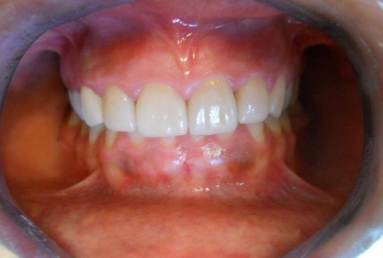

Porcelain veneers on all four upper incisors

Before treatment : inappropriate composite fillings on all four upper incisors, the patient will receive four porcelain veneers.